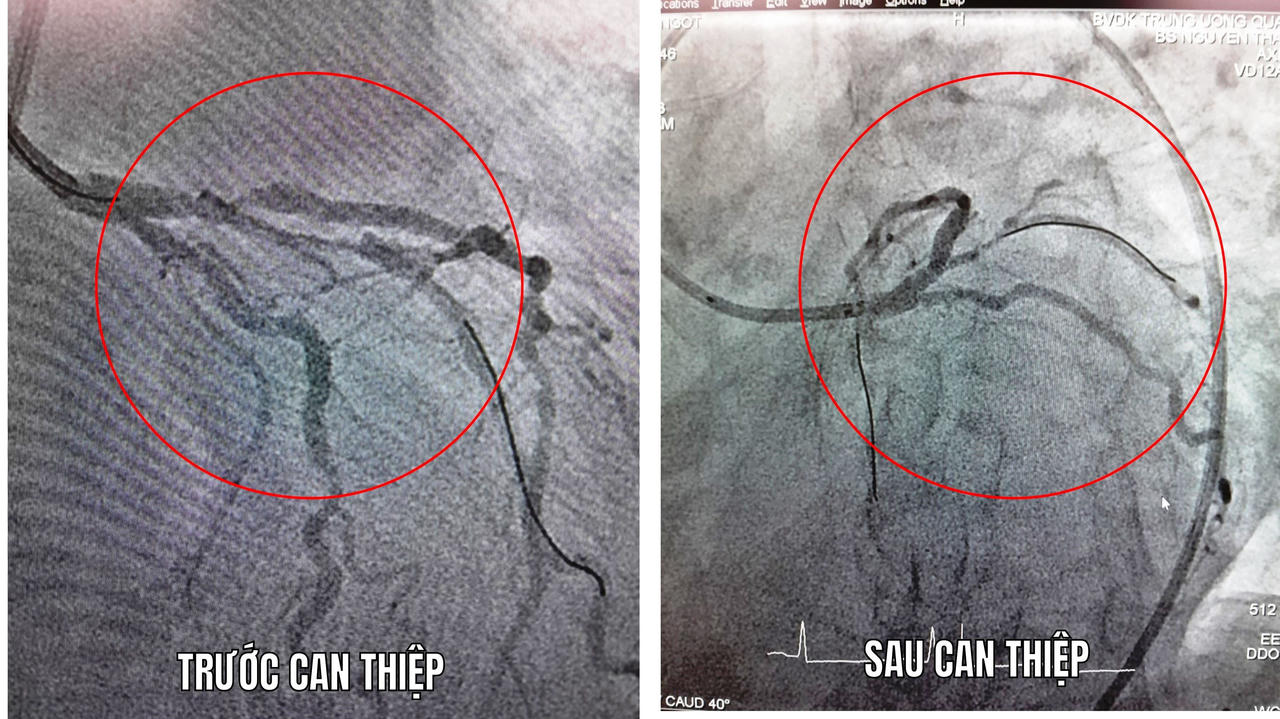

Tại phòng can thiệp, người bệnh lên cơn phù phổi cấp liên tục, được gây mê, đặt nội khí quản, thở máy và tiến hành chụp mạch vành cấp cứu cho kết quả là bán tắt lỗ vào động mạch liên thất trước (LAD) với dòng chảy qua rất chậm. Sau đó, người bệnh được can thiệp cấp cứu, trong lúc can thiệp người bệnh ngưng tim, tụt huyết áp liên tục. Vì vậy, các bác sĩ phải vừa hồi sức vừa can thiệp cùng lúc.

Hình ảnh mạch máu tim trước của người bệnh bị hẹp bán tắc LAD và sau can thiệp đặt 1 stent vào đoạn hẹp động mạch liên thất trước. |

Sau hơn 20 phút nỗ lực cấp cứu, bà N đã được can thiệp thành công khi được đặt 1 stent vào đoạn hẹp động mạch liên thất trước. Tiếp đó, bệnh nhân được chỉ định chạy thận cấp cứu nhằm tránh tình trạng phù phổi cấp tái lập và được chuyển về hồi sức thở máy.